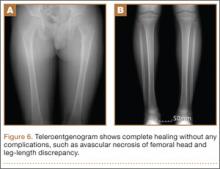

After screw removal, we recommended non-weight-bearing crutch-walking for 2 weeks followed by partial weight-bearing with crutch for another month. However, the patient started full weight-bearing 2 weeks after screw removal. One month after screw removal, he was brought to the emergency department with severe left hip pain after missing a step on a path. Anteroposterior and lateral radiographs showed an oblique subtrochanteric fracture at the empty screw holes (Figures 4A, 4B). A plate and 4 screws were placed to stabilize the subtrochanteric fracture, and a hip spica cast was applied and was to be worn for 3 weeks (Figures 5A, 5B).

At final follow-up, 6 months after the second surgery, the fracture was healed, and there had been no complications, such as avascular necrosis of the femoral head and leg-length discrepancy (Figures 6A, 6B).